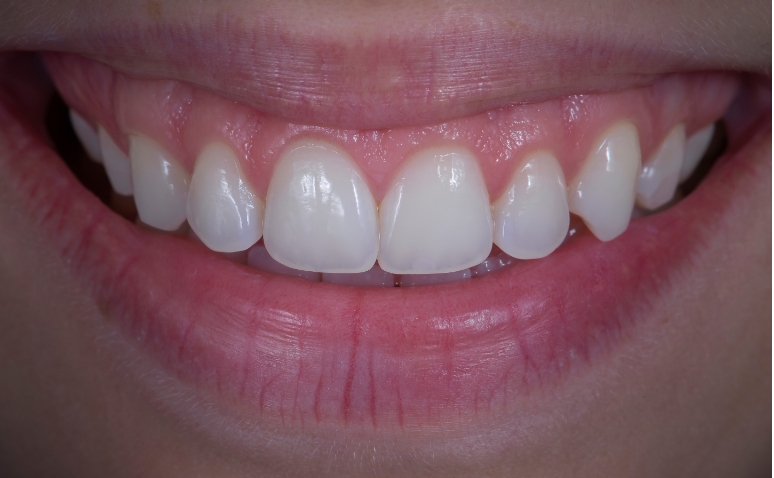

After

Before